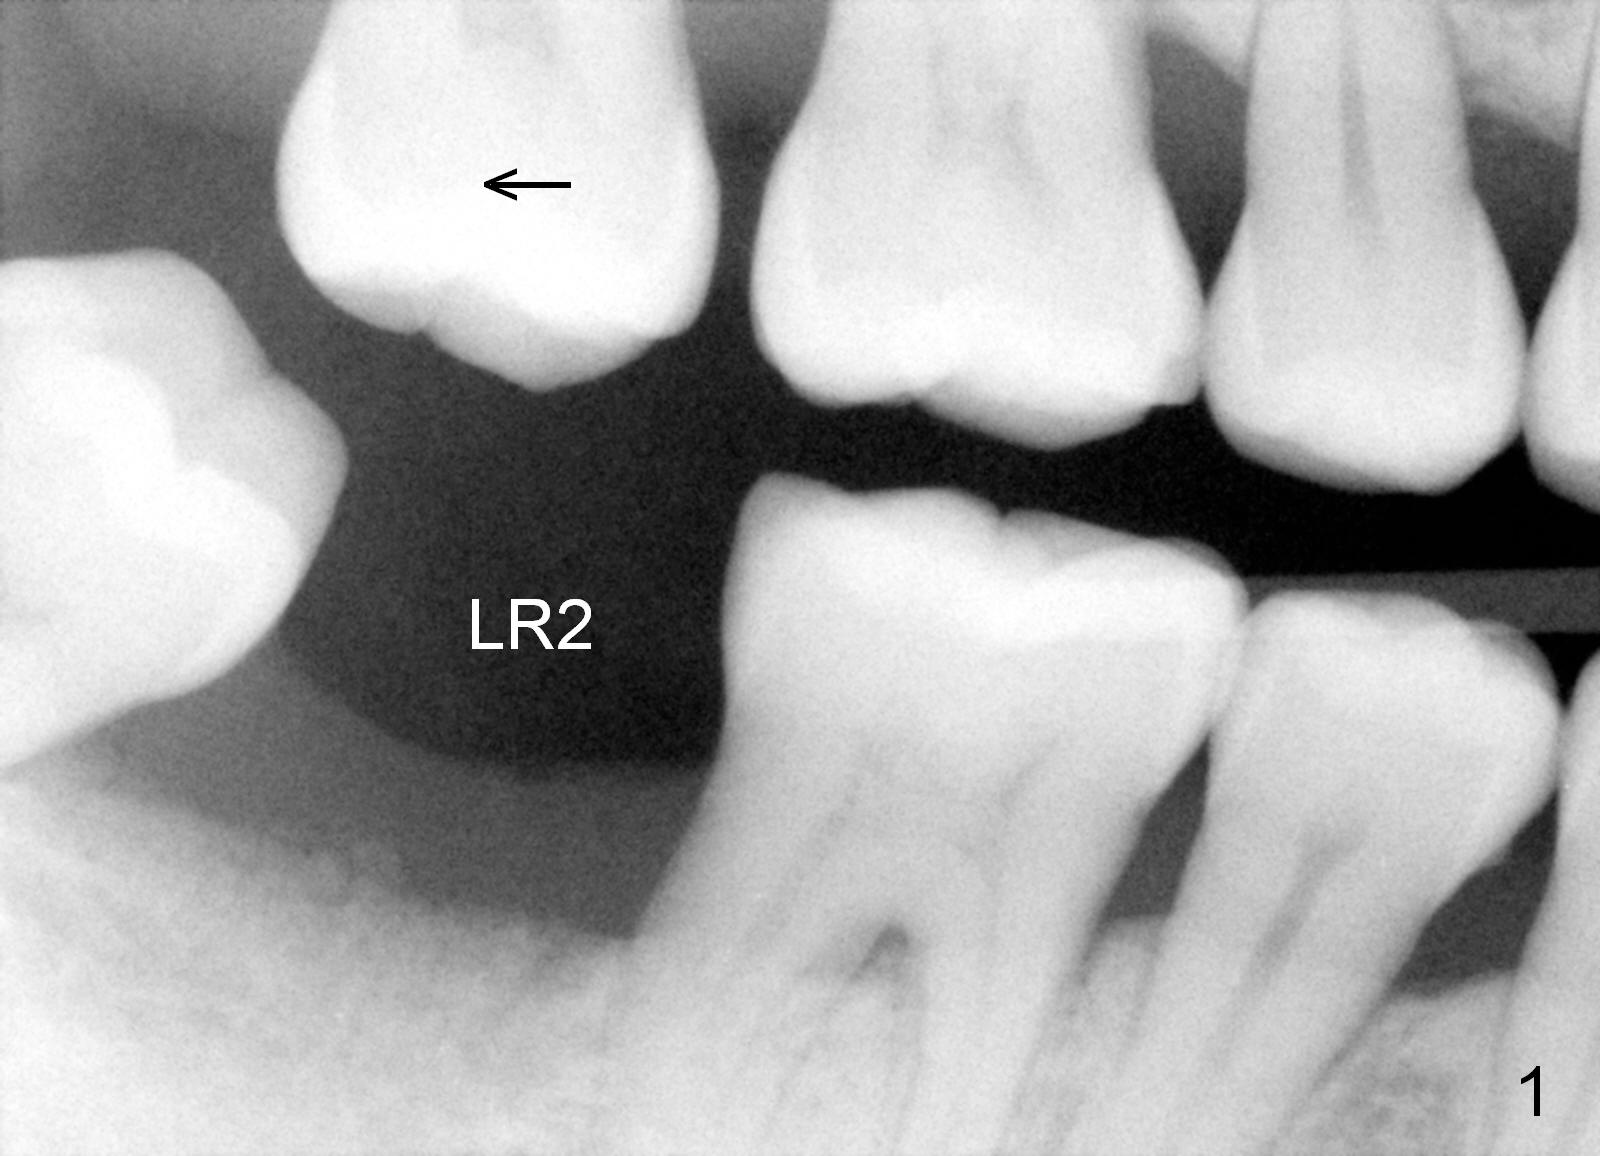

A 49-year-old lady is scared of dentistry. She presented with chronic periodontitis 7 years ago. The lower right 2nd molar had been missing (Fig.1 LR2), while the upper right 2nd molar shifted distally (arrow). Her chief complaint was mobility of #15 (Fig.2,4 UL2 with severe bone loss (*)). The tooth was extracted with expectation of return for implant placement in 6-8 weeks.

When she returns 7 years later, the tooth #2 has perio abscess with severe bone loss (Fig.3). She refuses to take antibiotic for infection control, but agrees to have immediate implant for #2 because of 1-staged surgery (Fig.5 I: 8x17 mm; A: abutment; P: bone powder (graft)). She is aware of delayed implants at the sites of #15 and 31 later. The bone height at the site of #15 reduces from 12 mm (Fig.4) to 7 mm (Fig.6) in 7 years.